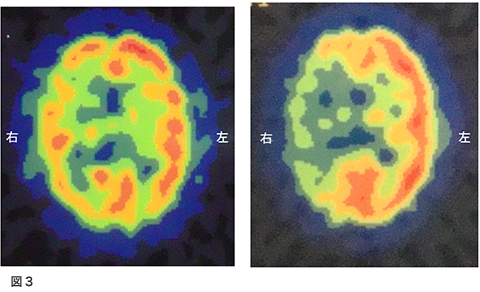

脳血流検査(SPECT)図3

左は、安静時検査、右がダイアモックス負荷時の検査です。安静時で右側の血流が低下していますが、ダイアモックスの負荷でさらに左右差が拡大しています。これは、盗血現象と呼ばれ脳循環予備能の強い障害を示します。